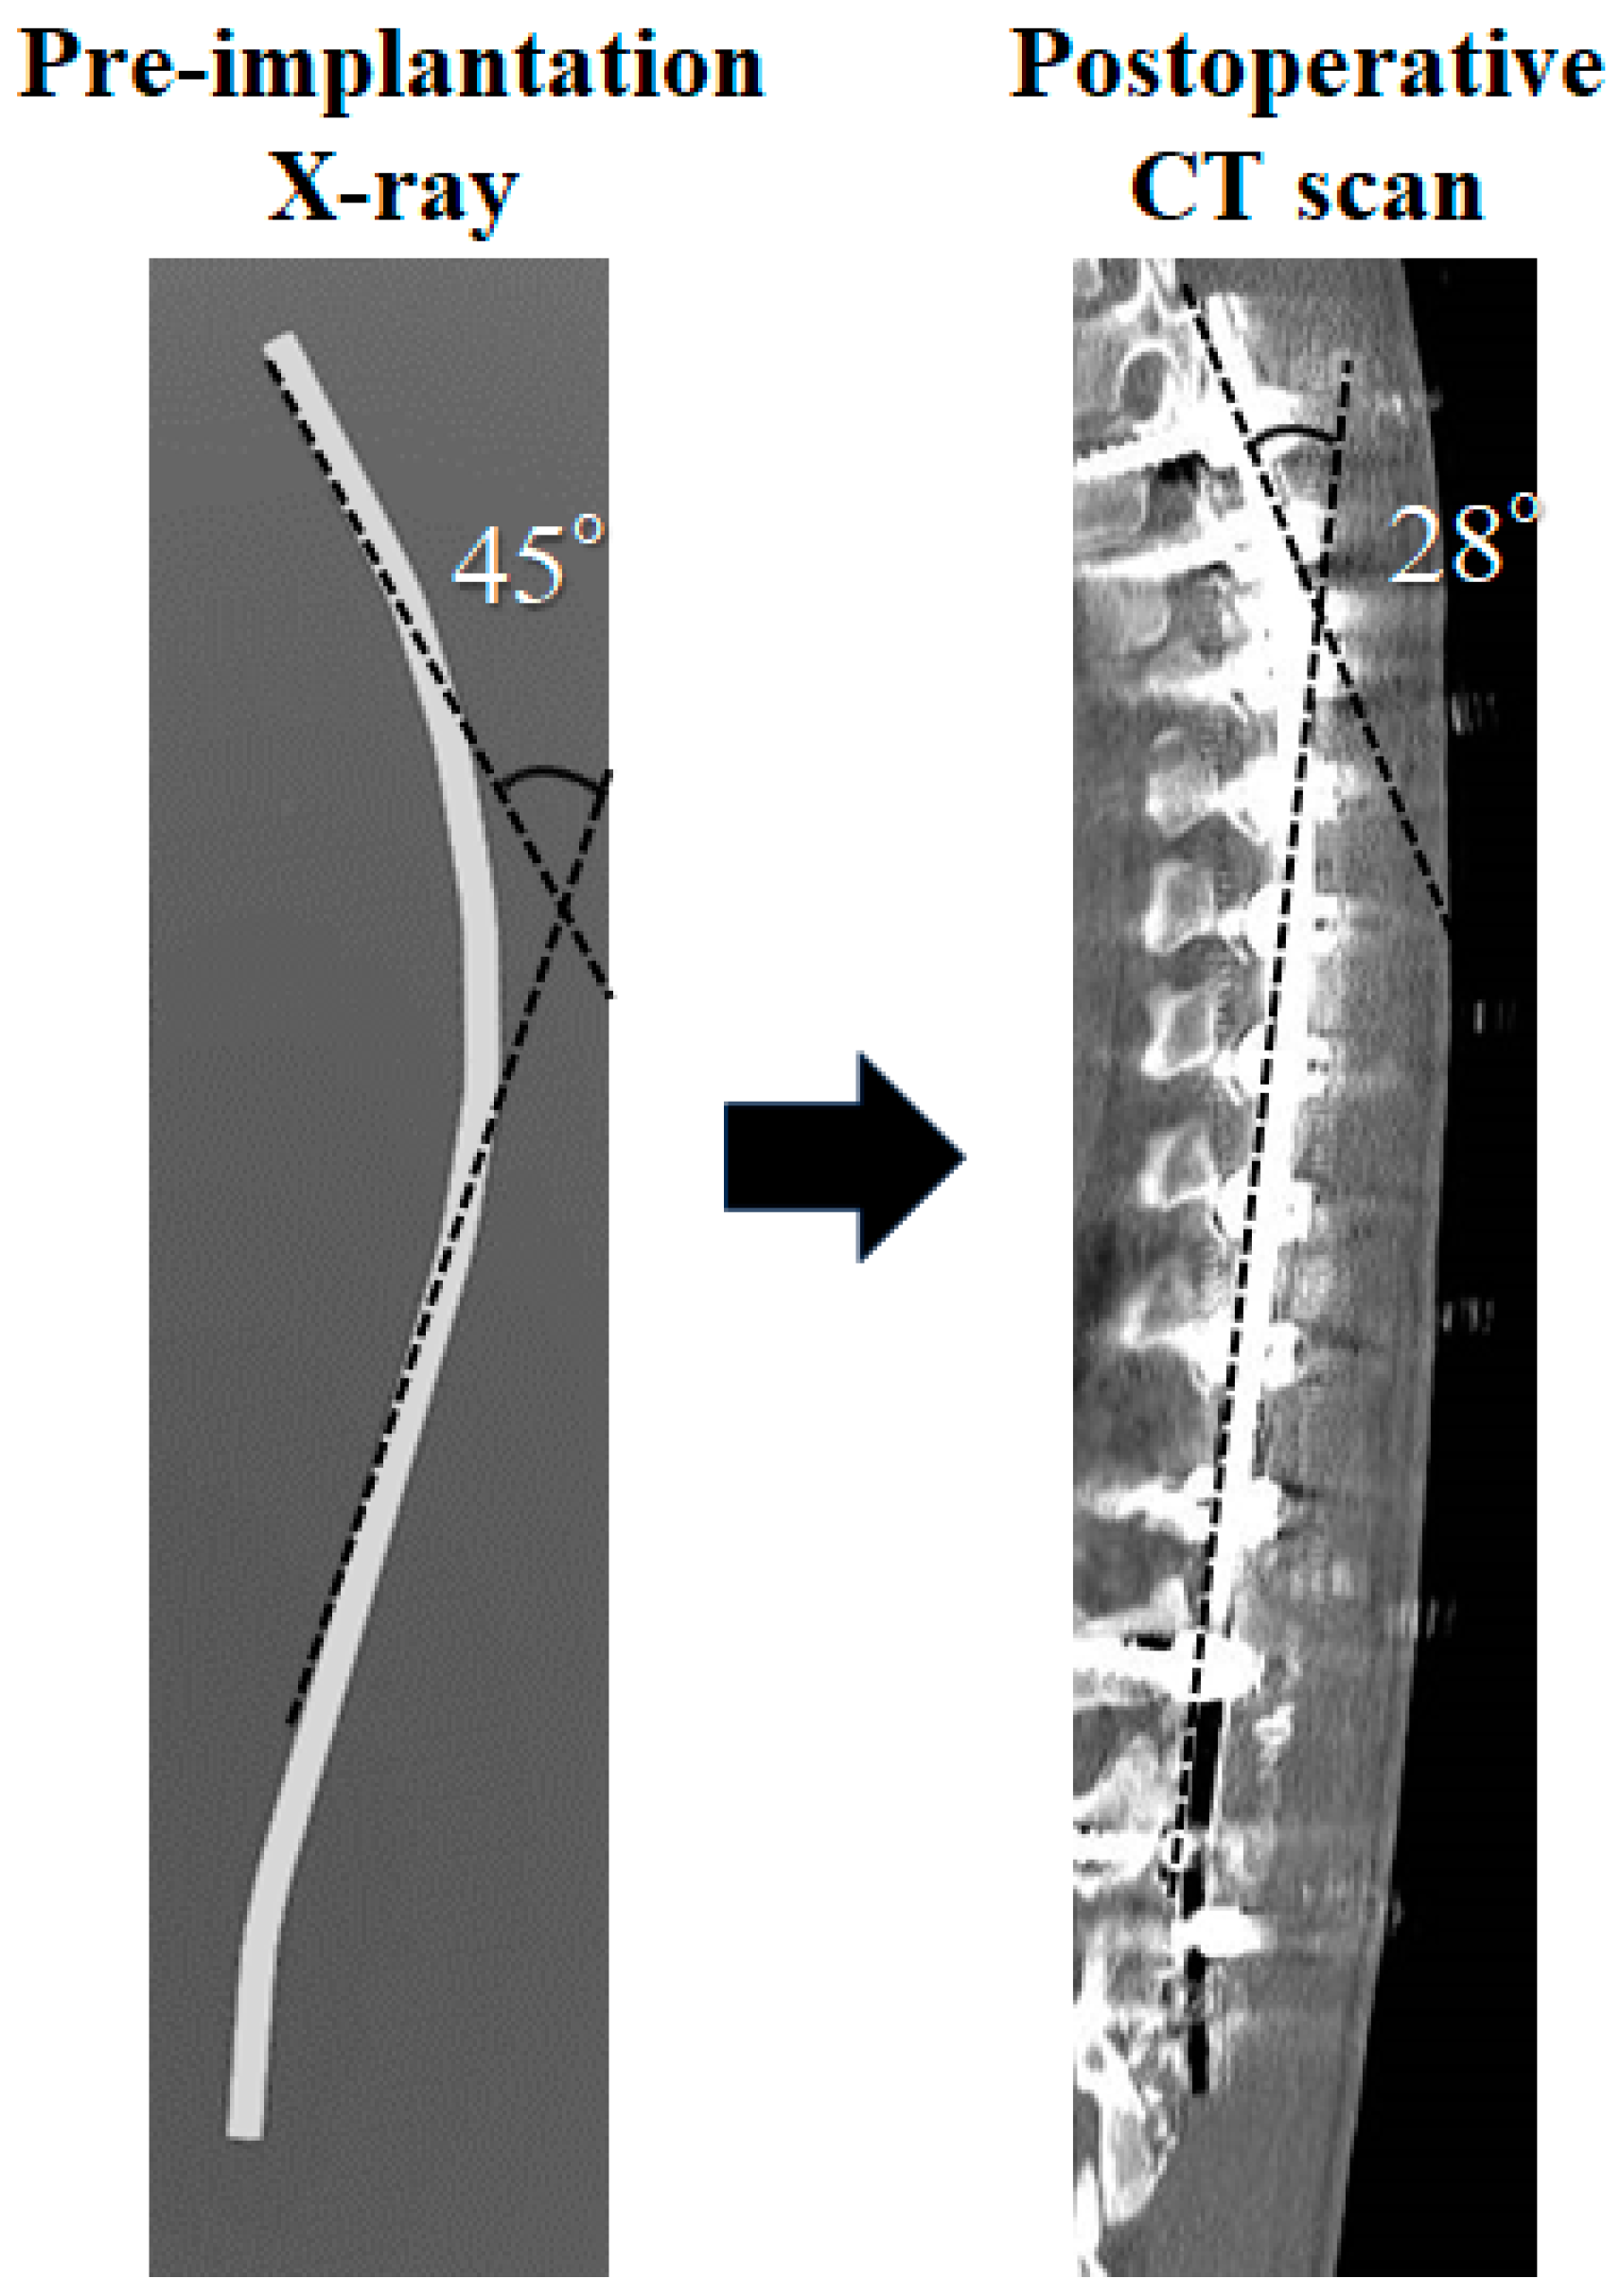

Adolescent idiopathic scoliosis (AIS) of the thoracic spine causes a three-dimensional deformity of the spine and ribcage. The treatment goal should be a well-balanced spine in all planes. The concave rod rotation (RR) technique has been developed in recent decades using Cotrel–Dubousset (CD) instrumentation [1] and the segmental pedicle screw fixation technique with RR, followed by direct vertebral rotation (DVR) [2,3]. Cidambi et al. [4] reported that rod contouring was significantly different between the concave and convex sides after surgery, with decreased curvature in the concave rod. They recommended the compensatory over-contouring of the concave rod for spinal correction in patients with AIS [4]. Differential rod contouring (DRC) is useful in improving vertebral rotation for posterior spinal fusion and correction in patients with AIS. The use of DRC with CoCr rods additionally improved apical rotation by almost 6° of apical rotation for thoracic scoliosis [5,6,7]. Overbending of the concave rod contour was significantly flattened after RR [8,9]. As shown in Figure 1, the concave rod measured 45° pre-implantation, while a postoperative X-ray and CT scan measured 28°. Convex rod deformation was not seen between pre- and postoperative images. CoCr rods have been reported to exhibit considerable stiffness compared to other materials such as titanium alloys and ultra-stainless steel, but they were still deformed after surgery [10,11]. Considering these facts, we considered that the 5.5 mm CoCr rod alone might not be able to sufficiently maintain the corrective force of the scoliotic spine through concave RR. Therefore, it was considered possible that sufficient rotation correction and kyphosis formation could not be achieved because the concave rod was deformed. For the above reasons, we have developed an outrigger device that prevents rod deformation during concave RR.

Figure 1.

This figure shows concave rod deformation. The concave rod was 45° before surgery. CT scan showed deformations of 28° after surgery. The convex rod was not deformed.

We analyzed the concave rod’s deformation during RR, as shown in Figure 1. The concave rod deformed by approximately 15° during RR due to the corrective force of the scoliotic spine [6]. The reduction force [34] and fatigue life [35] of the CoCr rod were stronger than those of titanium. The correctional force produced by the titanium 30° pre-bended rod was approximately 67% that of CoCr [34]. However, if the CoCr rod was plastically deformed after a reduction in rigid spinal deformity, the force of the CoCr rod in maintaining its original shape was lower than that of titanium, stainless steel, and ultrahigh-strength stainless steel [34]. This phenomenon suggests that it is important to prevent the plastic deformation of the concave CoCr rod. That is, the outrigger device may be useful for preventing the plastic deformation of the concave rod because the outrigger device that is removed after dual CoCr rods contains the main thoracic curvature. Our results also suggest that there were significant differences when obtaining the TK angles and apical five vertebral kyphosis between the groups using RR with and without an outrigger. These phenomena suggest that dual CoCr rods may continuously contribute to maintaining the contour of bended rods due to their stiffness. If titanium rods were used for correction, it is presumed that the results would be different. As far as we know, there have been no reports showing the effectiveness of outrigger devices that suppress plastic deformation during concave rod RR. However, if the scoliotic curvature was severely rigid, dual CoCr rods might be flattened after the outrigger device was removed. We cannot evaluate how much correction loss occurred after the outrigger device was removed because the outrigger device was not permanently attached. Therefore, further studies will be needed in the future.